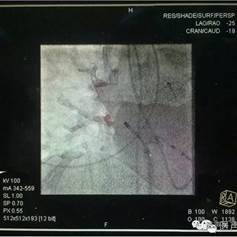

右上肺静脉消融补点及起搏验证,可于X线直视下展示消融导管头端与CT影像的空间相关性

动态影像融合引导房颤冷冻消融治疗

本次手术中,患者右肺分支比较多,通过影像融合CT导入,帮助我们准确判断了肺静脉分支的位置。射线量暂未观察到明显变化。但是,由于CT建模在心房舒张期,术中心房处于收缩舒张交替状态,为了确保模型和真实心脏运动完全贴靠,还需要继续探索和努力。